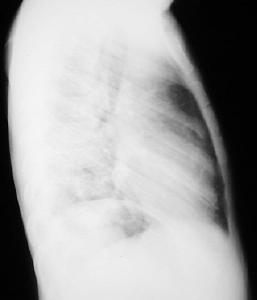

Radiología Pos - operatorio mediato, 7 dias :

Paciente estubado, drenaje toracico retirado, Pulmón izquierdo expandido, Observe el aumento de volumen del hemitorax izquierdo, la mayor amplitud de los espacios intercostales, la columna ya centrada, el diafragma izquierdo bien definido. Persiste discreta opacidad en base del hemitorax izquierdo.